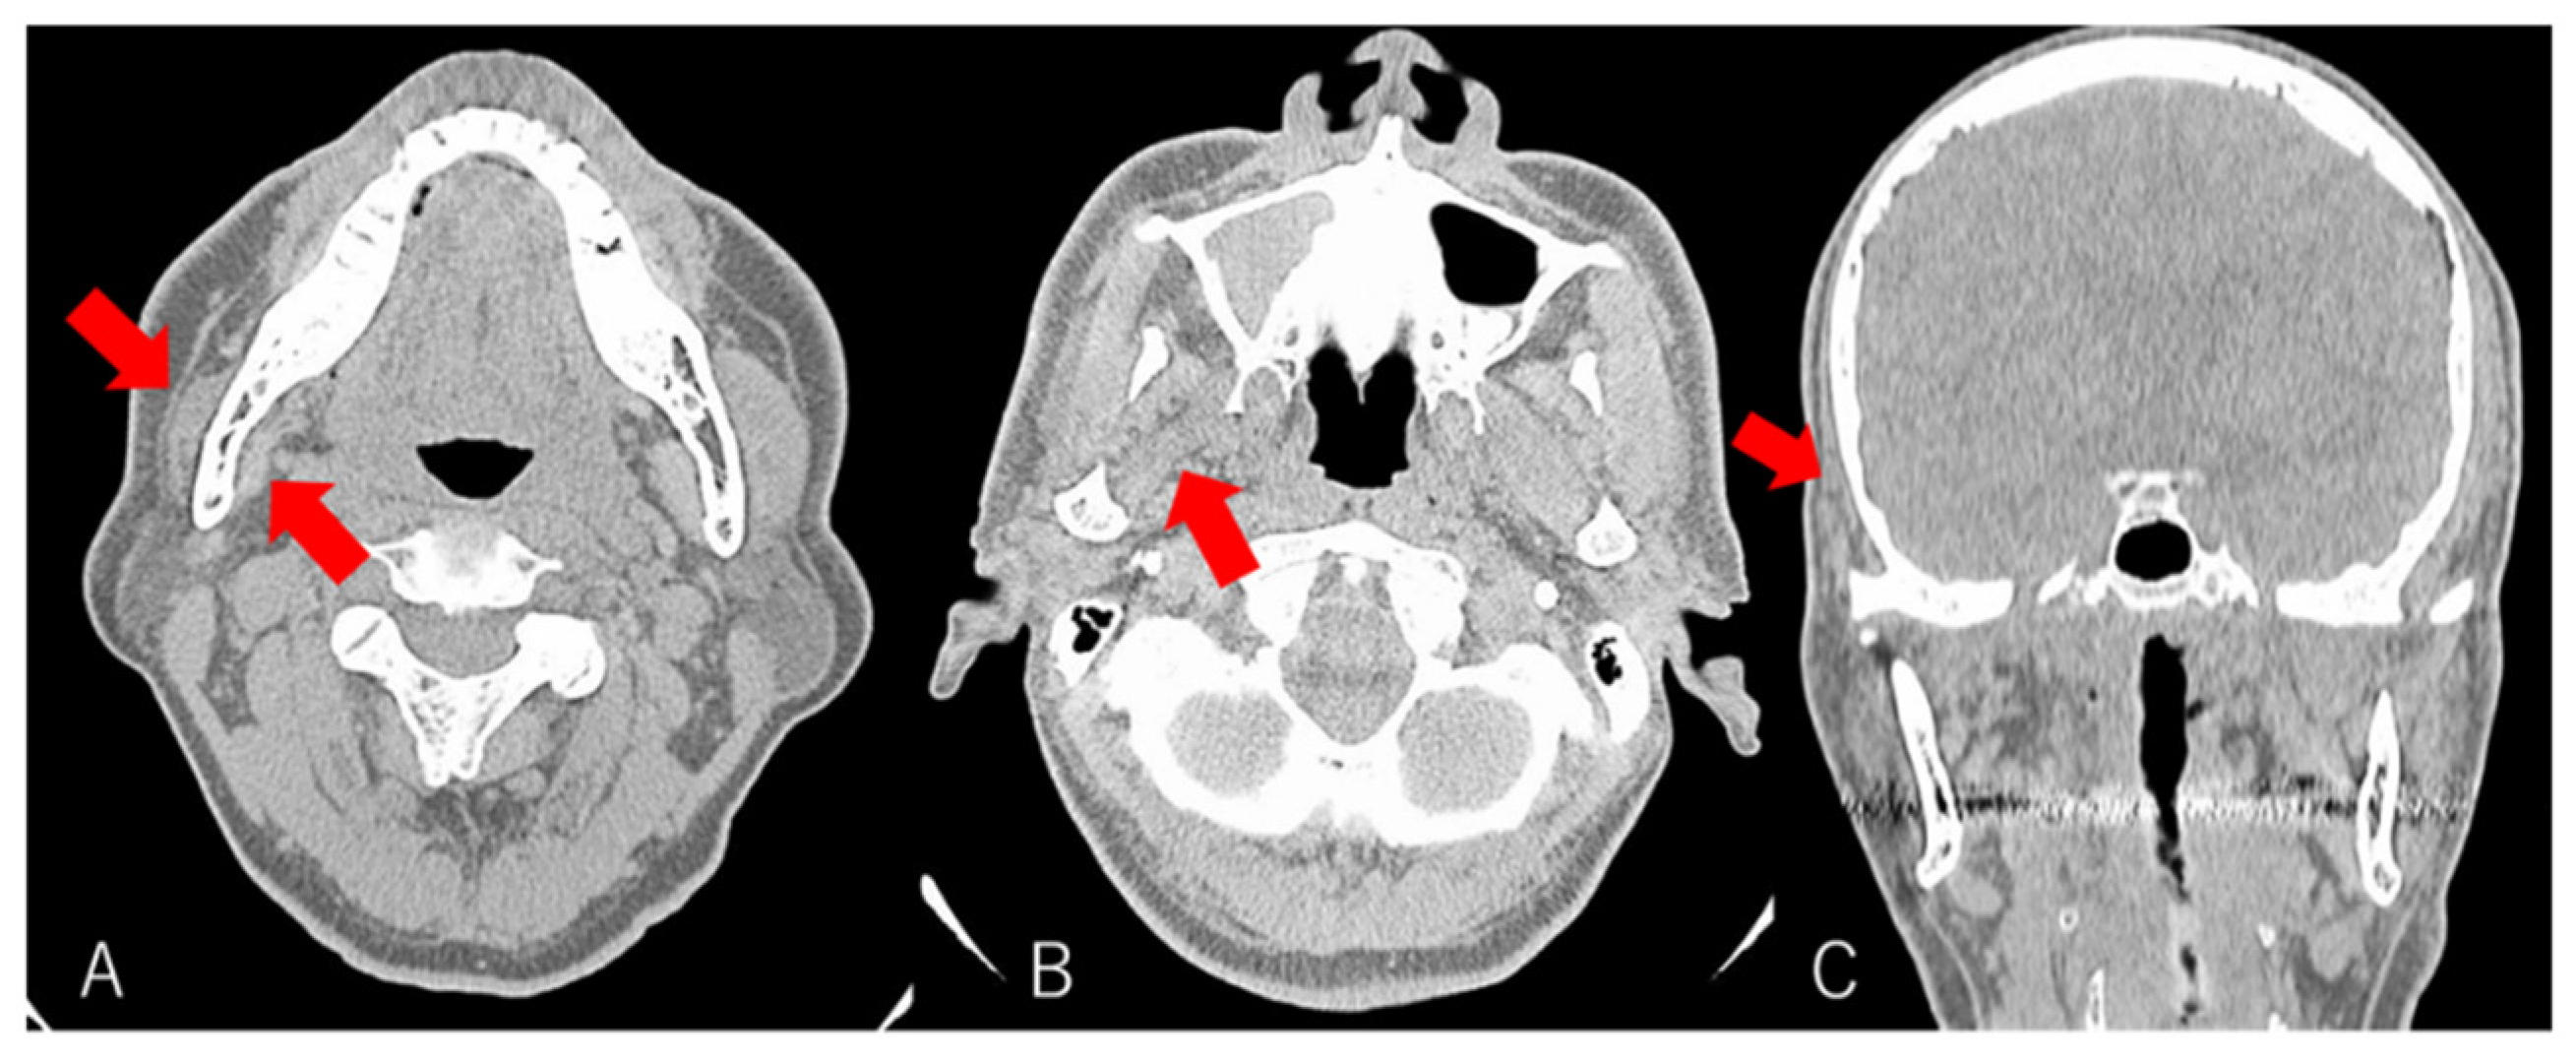

Panoramic radiographic findings were inconclusive for the presenting clinical symptoms (Figure 2). Computed tomography (CT) showed atrophy of the right masseter muscle, temporalis muscle, and lateral and medial pterygoid muscles (Figure 3). Blood tests were normal, and the patient tested negative for antinuclear antibody and rheumatoid factors. Physiological test results revealed bilateral hearing loss and paresthesia of the right side of the face. Surface electromyography recorded no action potentials in the right masseter and temporalis muscles (Figure 4).

Figure 3. Axial contrast-enhanced computed tomography (CT) of the soft tissue (A,B) and coronal CT of the head (C). Atrophy of the right masseter muscle, lateral and medial pterygoid muscles, and temporalis muscle (red arrow) compared with the contralateral side.